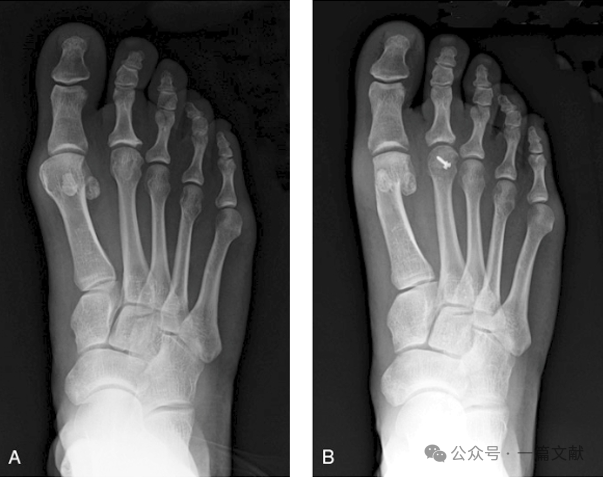

下图A 40岁女性,主诉为第二跖趾关节疼痛,X片显示第二跖骨头部轻度扁平改变。图B为行楔形截骨、螺钉固定术后6月复查X片。